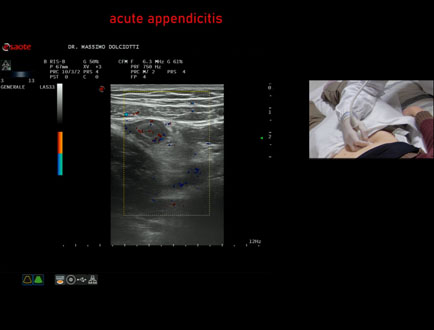

Data inserimento: 07/02/2025

Ecografia del: 03/02/2025

Strumento: Esaote MyLab Eight

Sonda: Lineare Multifrequenza 3-13 MHz

Età Paziente: M 8 anni

Motivazione dell'esame: da 3 giorni, febbre, vomito, dolori addominali

Commento all'esame: le immagini ed il video documentano, in sede ileo-cecale, appendice di spessore aumentato (6,5 / 8,5 mm - V.N. inferiore a 6 mm), numerose linfoadenomegalie locoregionali, delle dimensioni di 17,4 x 9,7mm, 14,4 x 6,7, 10,9 x 5,7 mm. Gli elementi ecografici segnalati orientano per appendicite acuta.

Conclusioni: appendicite acuta (acute appendicitis).

Presentazione: Dr. Massimo Dolciotti - Ancona